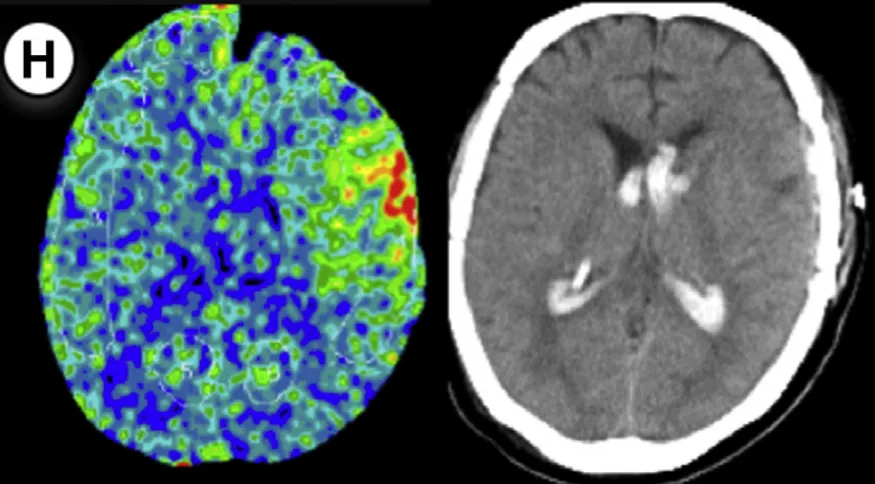

49岁男性,有TIA病史,行左侧大脑手术。方法1 rCBF增加率78%,方法2高达149%。术后第2天发现少量蛛网膜下腔出血,经1天镇静后出血未扩大。

26岁男性,有TIA病史,行右侧大脑手术。方法1 rCBF增加率63%,方法2达72%。术后第2天发现硬膜下血肿合并蛛网膜下腔出血,经1天镇静后出血吸收。

35岁女性,对侧大脑曾手术,行左侧大脑手术。方法1 rCBF增加率77%,方法2达67%。术后第2天发现出血合并脑室内出血,经预先规划的镇静干预未出现严重后果。